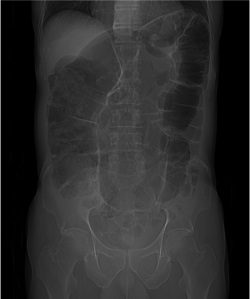

Radiografía simple:

Usada como screening, no excluye un diagnóstico de obstrucción intestinal si es normal.

La OI ha sido una de las indicaciones clásicas para la RA, que es diagnóstica en un 50-60% de los casos, dudosa en un 20-30% y confusa en 10-20% . La sensibilidad oscila entre el 46% y el 90.8% en las diferentes series, con especificidad próxima al 50%.

Los hallazgos principales serían dilatación de asas, niveles hidroaéreos y ausencia de gas distal. Las radiografías de tórax con hemiabdomen superior pueden usarse si existe sospecha de perforación. Tiene importantes limitaciones para determinar la causa de la obstrucion y la presencia de estrangulación.